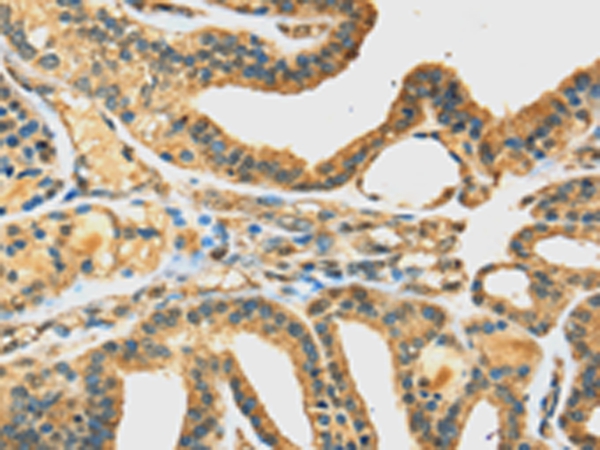

![DHCR24 Antibody[42747]](https://img1.dxycdn.com/p/s14/2025/0922/022/0466140736287600791.jpg)

Immunohistochemical analysis of paraffin-embedded Human thyroid cancer tissue using #42747 at dilution 1/35.